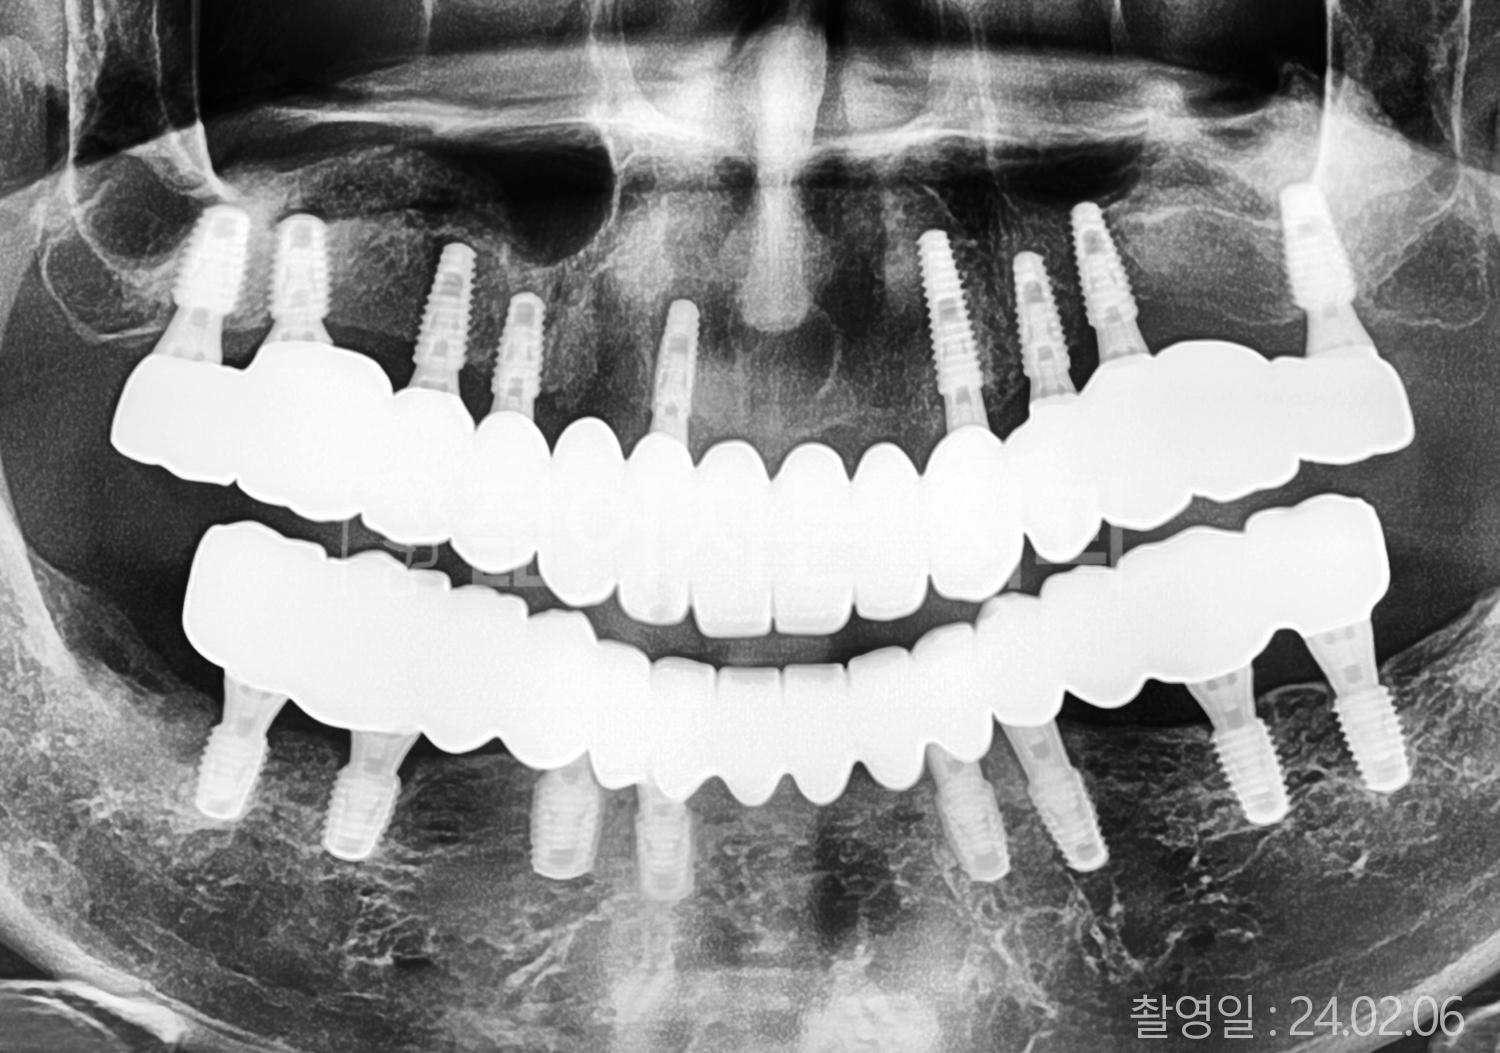

• 50대 전체치아 10개 이상 임플란트